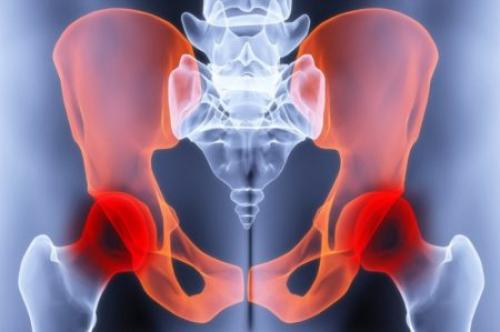

Коксартроз

Коксартроз – это постепенное разрушение и деформация поверхностей сустава. У человека болит нога в тазобедренном суставе при ходьбе или после нагрузки.

Со временем появляются ограничения подвижности (сложно отводить или поворачивать бедро наружу, сгибать и разгибать).

Боль чувствуется постоянно, не проходит в покое (бедро ноет, когда человек сидит или лежит, особенно на больном боку), возникает при вставании из положения «сидя», после длительного отдыха («стартовая» боль).

Сустав, пораженный коксартрозом. Нажмите на фото для увеличения